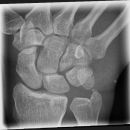

Hand a.p. (dorsovolar)

Beurteilungskriterien

- Kontinuität der drei Karpalbögen (vgl. Handgelenk):

Proximaler Bogen: proximale Gelenkflächenkonturen von Scaphoid, Lunatum und Triquetum

Mittlerer Bogen: distale Gelenkflächenkonturen von Sacphoid, Lunatum und Triquetum

Distaler Bogen: proximale Gelenkflächenkonturen von Capitatum und Hamatum

Fehlende Abgrenzbarkeit, Versatz oder Unterbrechung sind als pathologisch zu bewerten und deuten auf eine Luxation hin.

- M-förmiger Verlauf der Gelenkspalten der Carpometacarpalgelenke? Luxationsstellung in den Carpometacarpalgelenken (meist dorsale Luxation)?

- Gelenkspaltweiten der Carpometacarpalgelenke, der Metacarpophalangealgelenke und Interphalangealgelenke 1 –2mm, der Intercarpalgelenke 1,5 – 2mm

- Täuschungsmöglichkeiten durch Vielzahl akzessorischer Ossikel (abgerundete, zirkulkär-geschlossene Kortikalis), geteilte Handwurzelknochen (Scaphoid, Lunatum, Pisiforme) und Gefäßkanälchen

- Target areas leicht zu übersehender Frakturen:Processus styloideus radii et ulnae, Basen der Metacarpalia (v.a. MCP I) -> großzügige CT-Indikation, Hamulus

Cave: Metacarpale und phalangeale Rotationsfehlstellungen sind konventionell röntgenologisch schwer zu diagnostizieren und zu quantifizieren -> klinischer Befund führend (Fingerstrahl kreuzt bei Beugung im Grundgelenk den benachbarten Strahl), evtl. CT hilfreich.